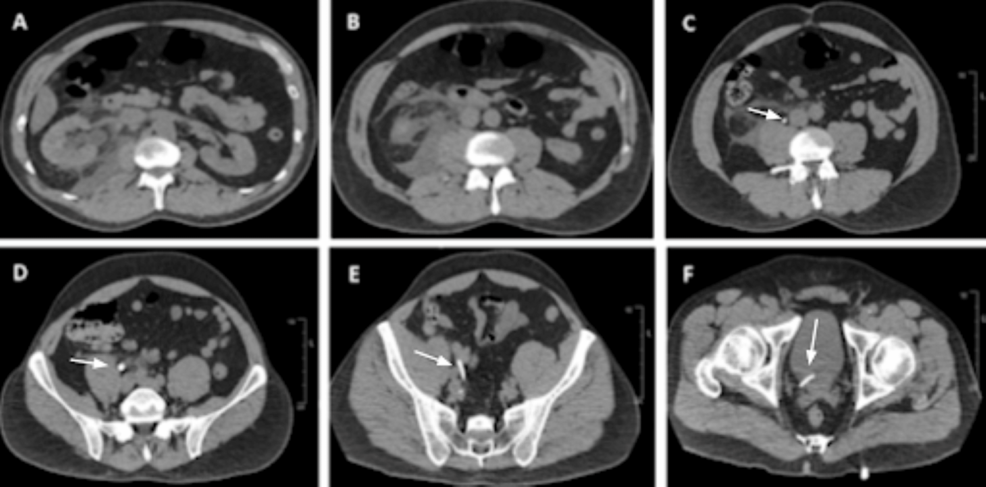

En el caso presentado, un paciente con antecedentes de ureterolitiasis se sometió a una TC sin contraste. La imagen reveló una estructura lineal que inicialmente se interpretó como un stent ureteral. Sin embargo, tras una evaluación más exhaustiva, se determinó que la estructura era en realidad contraste intravenoso retenido de un estudio previo.

Este hallazgo destaca la importancia de considerar el contraste intravenoso residual como una posible causa de artefactos en las imágenes de TC sin contraste. Los radiólogos deben ser conscientes de esta posibilidad para evitar diagnósticos erróneos y garantizar una atención adecuada al paciente.